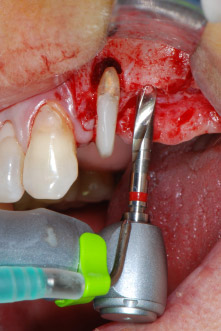

Nous avons toutefois maintenu notre projet initial de conservation des deux dents comme piliers temporaires d'un bridge pendant la période de six mois nécessaire à l'ostéointégration des implants. À la prochaine incision, la situation devrait être réétudiée. Premièrement, afin de gérer le problème endoparodontal, la surface de racine restante a été soigneusement débridée à l'aide d'un équipement piézoélectrique (Piezomed, W&H, utilisé avec l'insert en forme de spatule S1, initialement conçu pour limer la paroi sinusienne latérale) (Fig. 4).

Puis l'apex a été limé à l'aide du même instrument afin d'éliminer les tissus apicaux infectés résiduels et de réduire les éventuelles ramifications des canaux radiculaires (apicectomie) (Fig. 5). Il n'a pas été nécessaire de procéder à une obturation rétrograde car l'obturation orthograde venait juste d'être reprise.